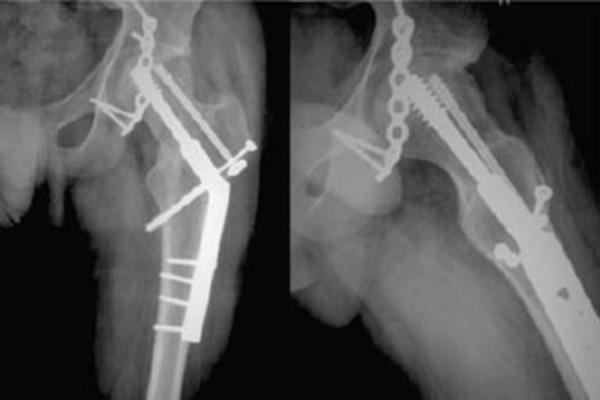

We report an unusual case of fracture dislocation of hip in which posterior dislocation of hip was associated with fracture of acetabulum, femoral head, femoral neck, greater trochanter and ipsilateral shaft of tibia. The fracture dislocation was managed with open reduction and internal fixation. Such fracture dislocation has not been reported in literature to the best of our knowledge.

我们报告一例罕见的髋关节骨折脱位病例,该病例为髋关节后脱位并伴有髋臼、股骨头、股骨颈、大转子及同侧胫骨干骨折。该骨折脱位采用切开复位内固定治疗。据我们所知,此类骨折脱位在文献中尚无报道。